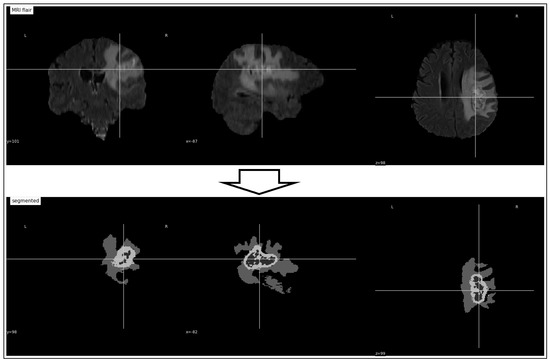

3.1. Pre-Processing

3.2. Tumor Identification